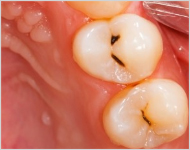

补牙,是常见的牙齿修复术,许多人的牙齿出现龋坏、缺损等情况,较好的方式就是补牙。由于每个人的口腔状况不同,医生需要根据患者的具体牙位、龋齿的洞型、牙齿的缺失等情况来选择相对应的治疗方法来进行修复……【详细】

深圳博愛曙光口腔專家表示:採取補牙術是為了阻止齲齒繼續惡化。所謂補牙就是採用用人造物質修補牙體缺損的方法,用於修補的物質叫充填材料。凡因齲齒、楔狀缺損、外傷等造成牙體組織缺損者都需要修補,以恢復其外形和功能。